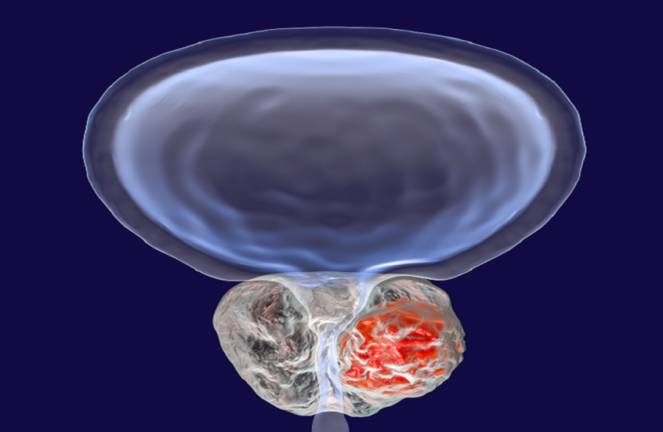

وجدت دراسة حديثة أن تناول الأطعمة فائقة المعالجة قد يزيد من خطر إصابة الرجال بتضخم

وفي الدراسة، قارن الباحثون النظام الغذائي لنحو 77951 رجلا بريطانيا تزيد أعمارهم عن 45 عاما على مدى عشر سنوات، وشُخّص 7387 منهم بتضخم البروستات الحميد.

وأظهرت النتائج أن زيادة استهلاك الأطعمة فائقة المعالجة بنسبة 10% ارتبطت بارتفاع خطر الإصابة بتضخم البروستات الحميد بنسبة 4%.

وفي المقابل، وجد الباحثون أن زيادة استهلاك الأطعمة النباتية غير المصنعة بنسبة 10% ارتبطت بانخفاض خطر الإصابة بنسبة 9%.

وأوضح الباحثون من مستشفى جامعة بكين في شنتشن بالصين ومراكز أخرى، أن هذه أول دراسة تربط بشكل مباشر بين الأطعمة فائقة المعالجة وخطر الإصابة بتضخم البروستات الحميد، مشيرين إلى أن هذه الأطعمة قد تؤثر سلبا في صحة البروستات.

وأشاروا إلى أن ارتفاع نسبة الأطعمة فائقة المعالجة في النظام الغذائي قد يعزز الالتهابات المزمنة ومقاومة الإنسولين، ما قد يساهم في تضخم البروستات، إضافة إلى احتمال وجود تأثيرات ناتجة عن اضطرابات التمثيل الغذائي.

وأضاف أن هذا المرض أكثر شيوعا من سرطان البروستات، وقد يسبب أعراضا مزعجة تتطلب علاجا دوائيا أو جراحة، ما قد يترتب عليه تكاليف وآثار جانبية.